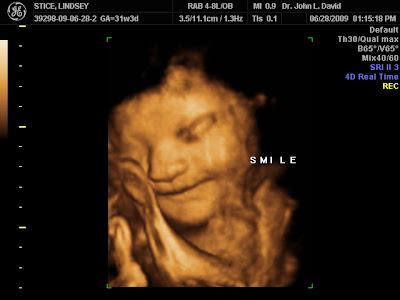

Cooper Westin Stice in 3D

Today, we went & had our 3D/4D sonogram done. It was ahhhh-mazing, as usual. However, he was a little bit stubborn, border-line misbehaving!! We were trying to get him to come out of hidding so we could get some good photos of him. However, he wanted to be a snuggle-bunny and hide his face!! He lays with 1 or both hands near or under his face (just like me!). So, his hand got in the way of quite a few pictures. We got 2 color photographs, 44 b+w (typical sono -style) photographs, 108 digital jpegs (we can print them), and a 1 hour long DVD of the whole session! It was great - definitely a keepsake forever - if I don't wear it out before then! :) Here are a few of my favorites...